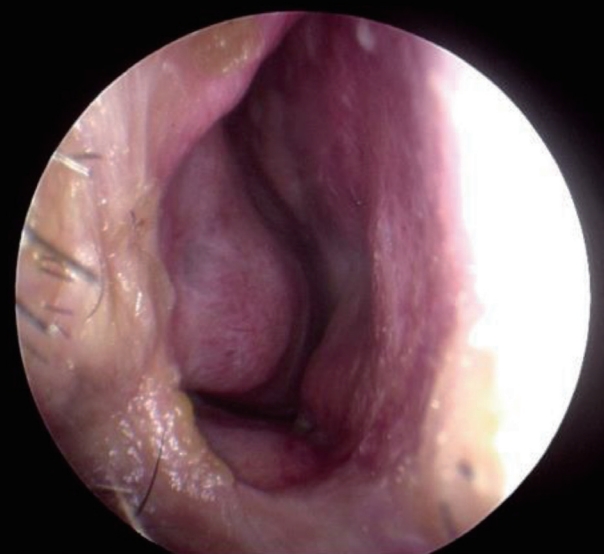

We performed endoscopic mass removal through the right nasal cavity. After an incision was placed in the right ala, the mass and the mucous membrane surrounding the mass were carefully peeled off and completely removed (Fig. 4). Histological examination confirmed the diagnosis of a myxoma (Fig. 5). After 9 months of surgery, patient is being followed up without complications or cosmetic problems (Fig. 6).